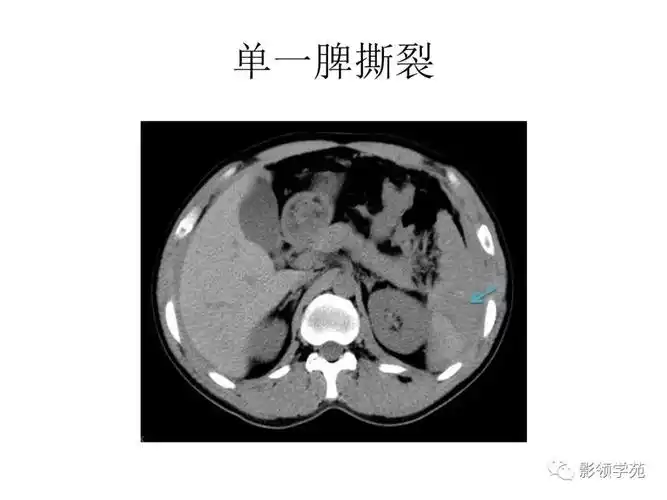

张阿姨腹部ct显示:脾脏破裂,腹腔积血.

脾脏破裂,周围积血.

ct表现包膜下破裂中央破裂完全性破裂分类脾破裂肾脏泌尿系统胰腺肝脏